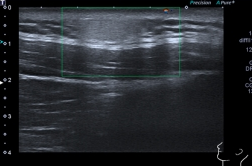

脂肪瘤对超声医生来说可是老朋友了,一般很快就能够作出诊断。根据脂肪瘤脂肪成分和支持成分的不同,在超声图像上可能表现为低回声或高回声的椭圆形或扁形肿块,特征性表现是内部有平行于皮肤的线状稍高回声,肿瘤内多无血流信号,少数可见点状的血流信号。

颈根部脂肪层内见高回声,边界清晰,内回声均匀。CDFI显示肿块内未见明显血流信号